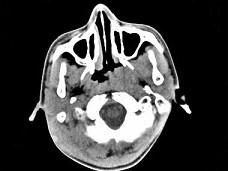

问题 男,17岁,自诉鼻涕中带血3个月,伴耳闷、听力减退,无发热。如图所示鼻咽部病灶最可能的诊断为 ( )

选项 A、小唾液腺混合瘤 B、鼻咽部淋巴组织增生 C、鼻咽部恶性淋巴瘤 D、鼻咽癌 E、咽旁脓肿

答案 D